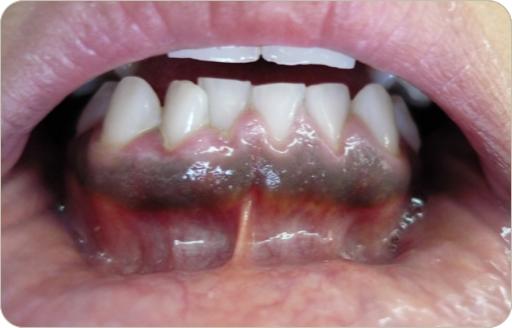

En este mes tenemos tres casos, dos son clínicos y uno es radiográfico, esperamos tu participacion al correo patobu1@hotmail.com o